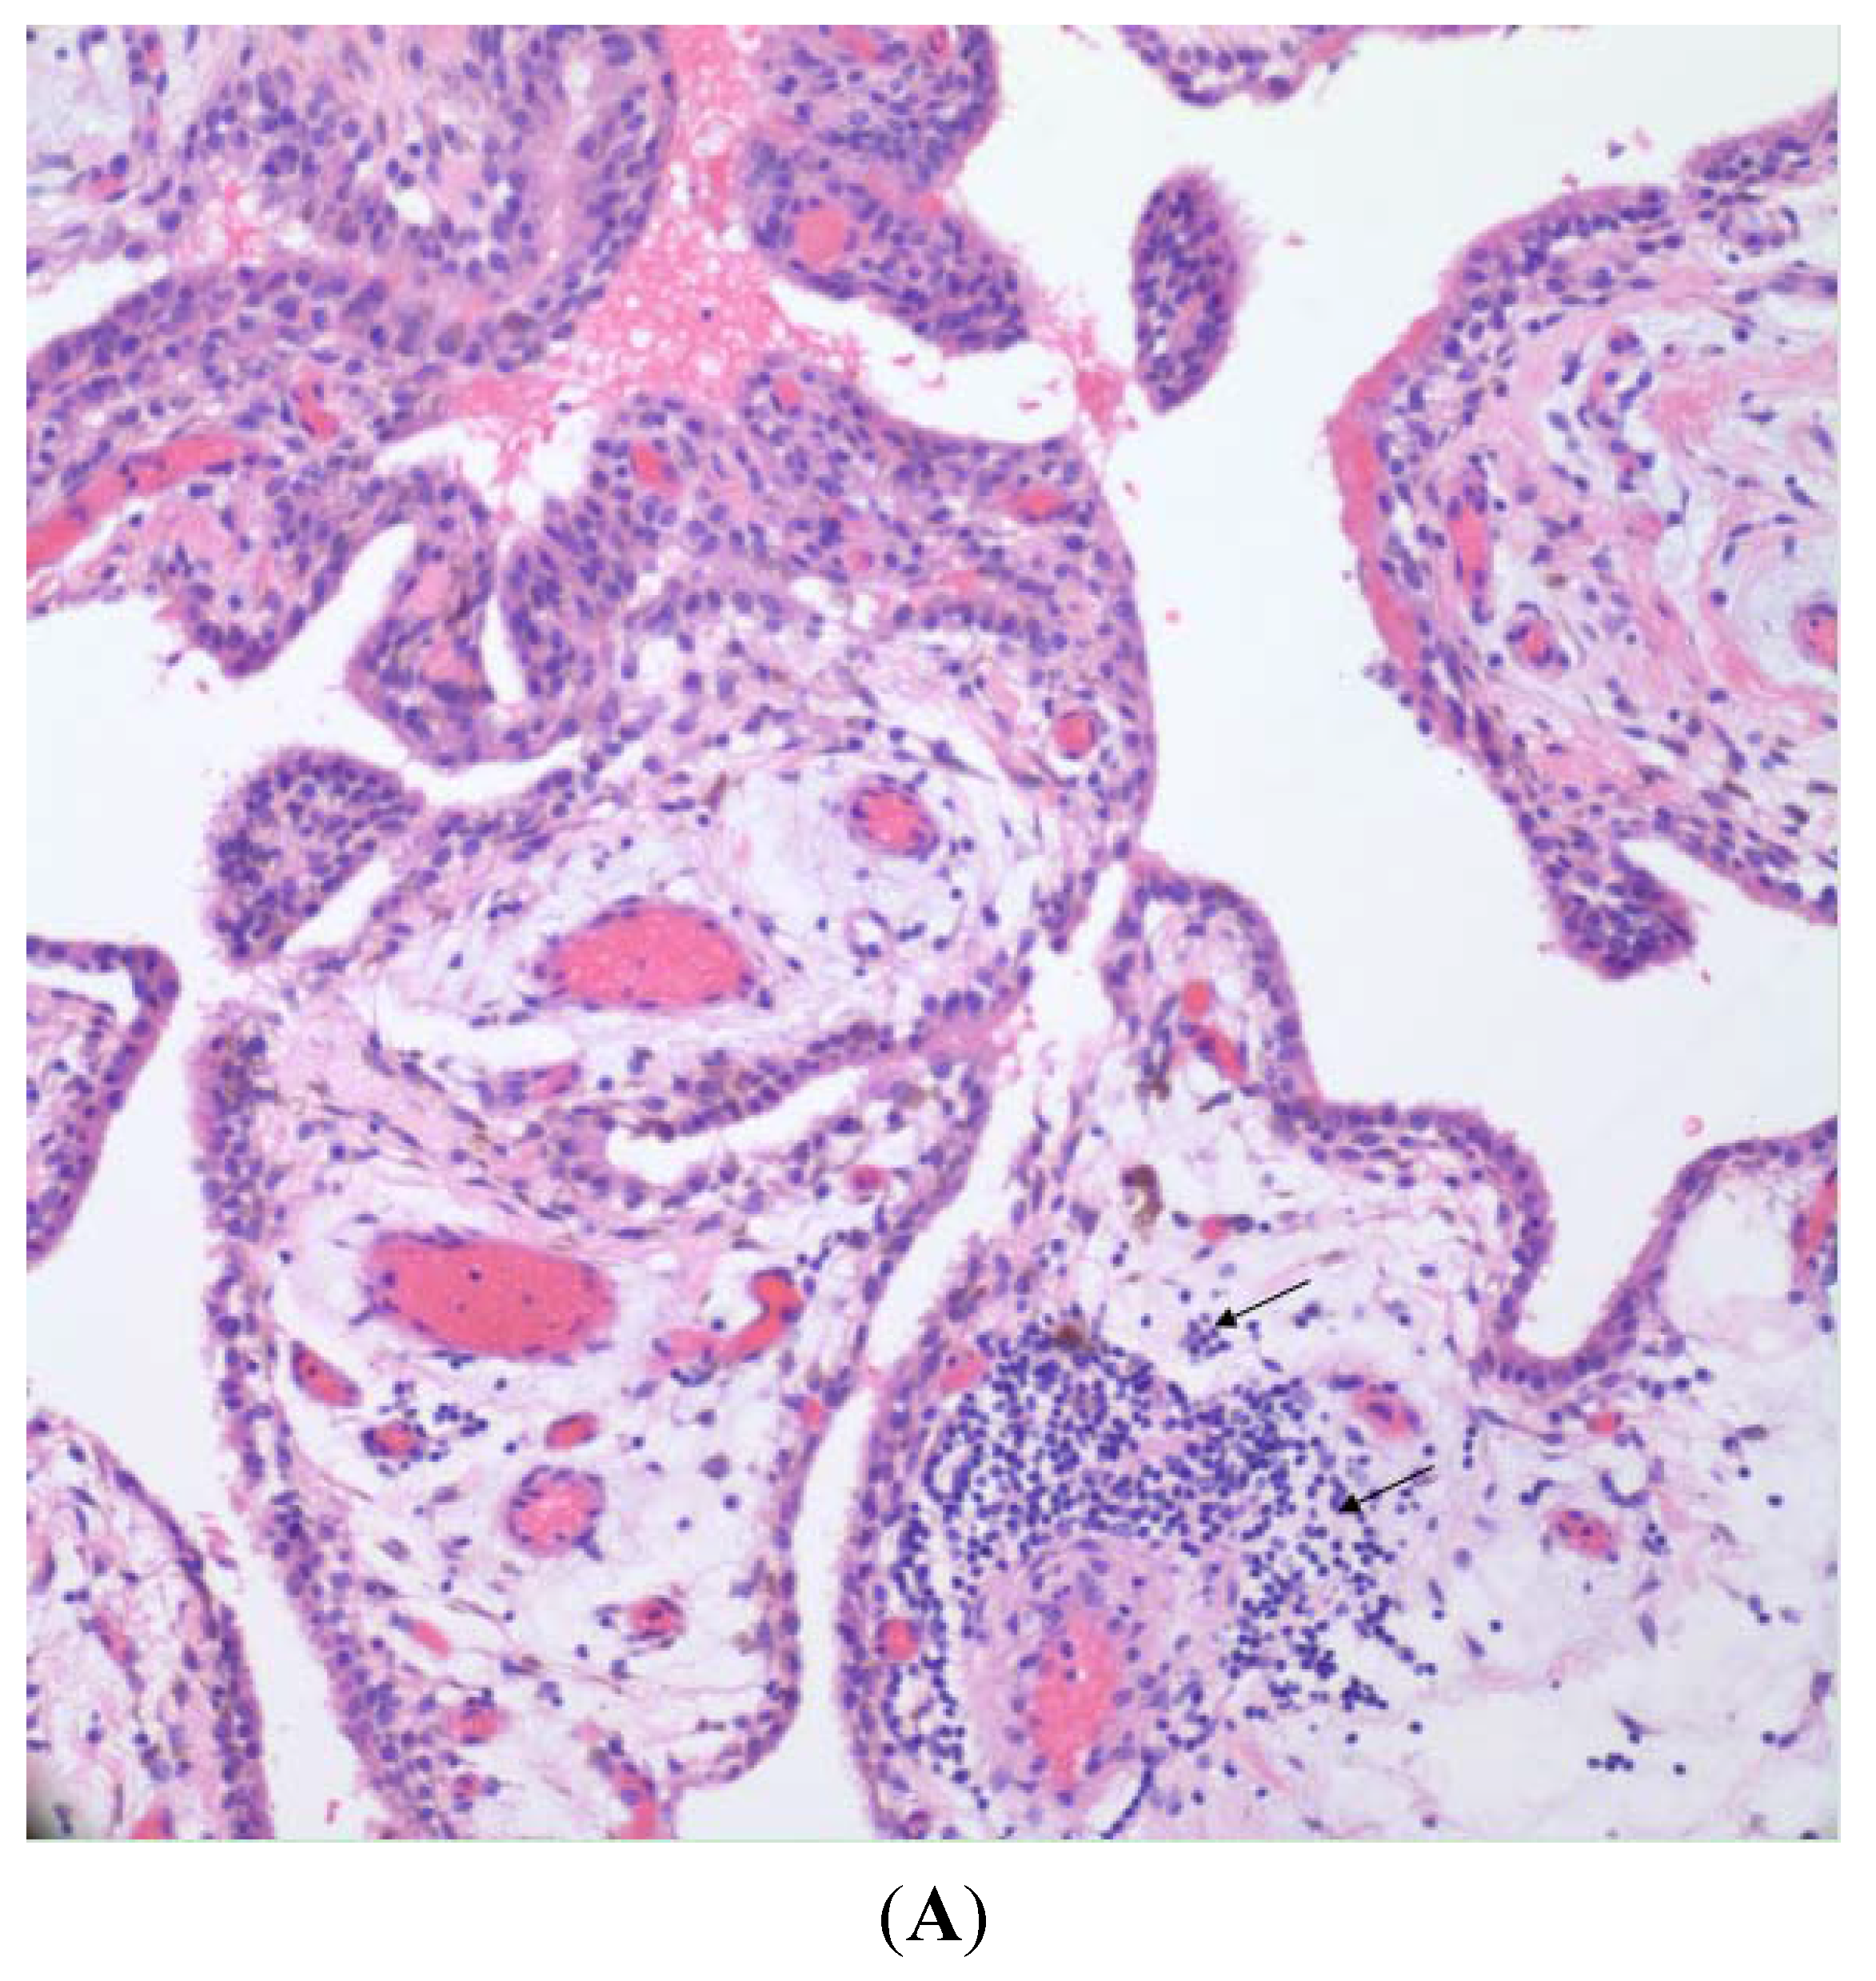

Figure 3 shows light micrographs of synovial tissue from an osteoarthritic joint prior to metal-on-polyethylene joint replacement (Figure 3A) and then following revision of that joint replacement (Figure 3B) in the same patient. Microscopic examination of both pre- and post-revision specimens in this patient shows an intimal/synovial lining with an underlying, non-specific, lymphoplasmacytic, chronic inflammatory infiltrate adjacent to, or centered around blood vessels. The post-revision specimen displays a denser collagenous subintimal layer (Figure 3B). Also present in the post-revision tissues are fragments of polarizable polyethylene with accompanying chronic inflammation including foreign body giant cells (Figure 3C).

(A) Pre-revision specimen showing synovial lining with intact intimal layer and non-specific chronic inflammatory infiltrate (H&E 200×); (B) post-revision specimen showing intact intimal layer, denser subintimal collagenous tissue, and non-specific chronic inflammatory infiltrate (arrows) (H&E 200×); and (C) post-revision specimen, deep to the synovial lining showing multiple fragments of polyethylene with accompanying chronic inflammatory infiltrate including foreign body giant cells (H&E, polarized, 200×).